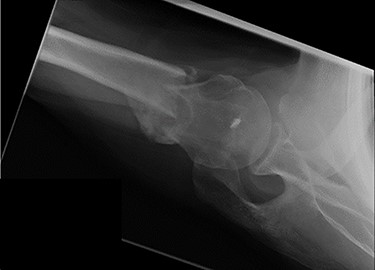

An X-ray of the left shoulder was performed, which revealed acceptable positioning of the fracture. Following a discussion with the patient, a mutual decision was made to manage the injury non-operatively and he was discharged with a collar and cuff sling. Subsequent clinical and radiological review at 1 week and 2 weeks post-injury showed the soft tissues to be healing well and the fracture to be well-positioned (Figs 5 and 6).

Antero-posterior view X-ray taken 2 weeks post-injury showing acceptable positioning of the fracture.